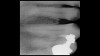

(16.) Photograph of failing implant prosthetics that may require specialty care taken with a smartphone and an EALS device.

Figure 16

(17.) Photograph of failing implant prosthetics that may require specialty care taken with a smartphone and an EALS device.

Figure 17

Emergency visits are a common and unpredictable occurrence at nearly all dental practices (Figure 14 and Figure 15). When an emergency occurs, the patient's provider may not always be available to evaluate and initiate treatment. In a similar manner, new patients of record frequently present with oral conditions that require the attention of a dental specialist who may only be available at another clinic (Figure 16 and Figure 17). For many of these patients, immediate access to care may be limited, and if a patient is experiencing discomfort, time will be a critical factor in regard to initiating a proposed plan of action. The use of a smartphone with an EALS can allow the clinical staff to rapidly acquire intraoral photographs or a video and transmit these images and other information via encrypted text message or secure e-mail to anywhere in the world for immediate consultation. The combination of telecommunications and dentistry is known as teledentistry,13which has been shown to impart significant benefits to patients and providers in the fields of oral medicine,14 oral and maxillofacial surgery,15 endodontics,16 prosthodontics,17 periodontics,18 pediatrics,19 orthodontics,20 and oral hygiene.21